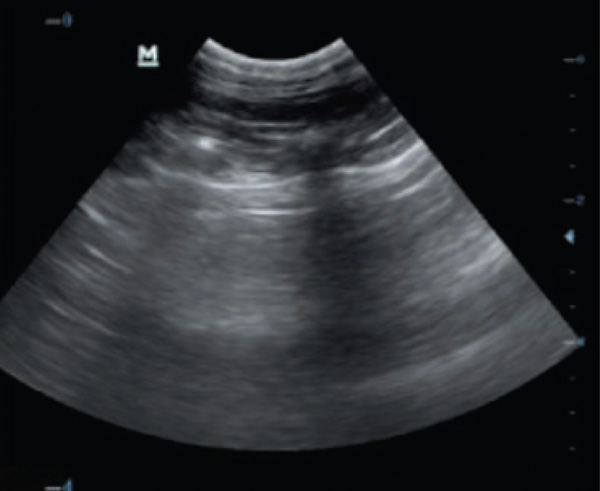

Point-of-care ultrasound is a tool to be used alongside the physical examination in the initial assessment of the dyspnoeic patient. No clipping is required, instead parting the fur and application of spirit to the skin should provide adequate contact for the probe. Placement of the probe in the rib spaces at numerous places dorsally and ventrally in numerous sites on both the left and right hemithorax will allow for assessment of pleural space disease and pulmonary disease. Pleural effusion and pericardial effusions can be identified easily as largely anechoic areas (Figure 3a). However, exudates may appear to be more echogenic. Ultrasound features of lung disease include the presence of ‘B lines’ or 'comet tails’ obliterating the normal ultrasound-gas interference (Figures 3b and 3c) With practice, cardiac chambers and the presence of a ‘glide sign’ can also be assessed on point-of-care ultrasound. Placement of the probe vertically between the ribs on the right hemithorax over the apex heartbeat allows visualisation for the four chamber view and then, with movement of the probe horizontally and cranially, the left atria to aorta ratio can be assessed. This requires practice and care should be taken to ensure correct chambers are identified before attempting a measurement. Increased left atria to aorta ratio suggests cardiac disease as strongly as the case of dyspnoea (Figure 4). A glide sign or ‘sliding lung’ represents the pleural-pulmonary line and in the absence of pleural space disease the lung glides along the thoracic wall as the patient breathes in and out. Absence of this line is suggestive of a pneumothorax.

Figure 3b. A lines on normal lung ultrasound